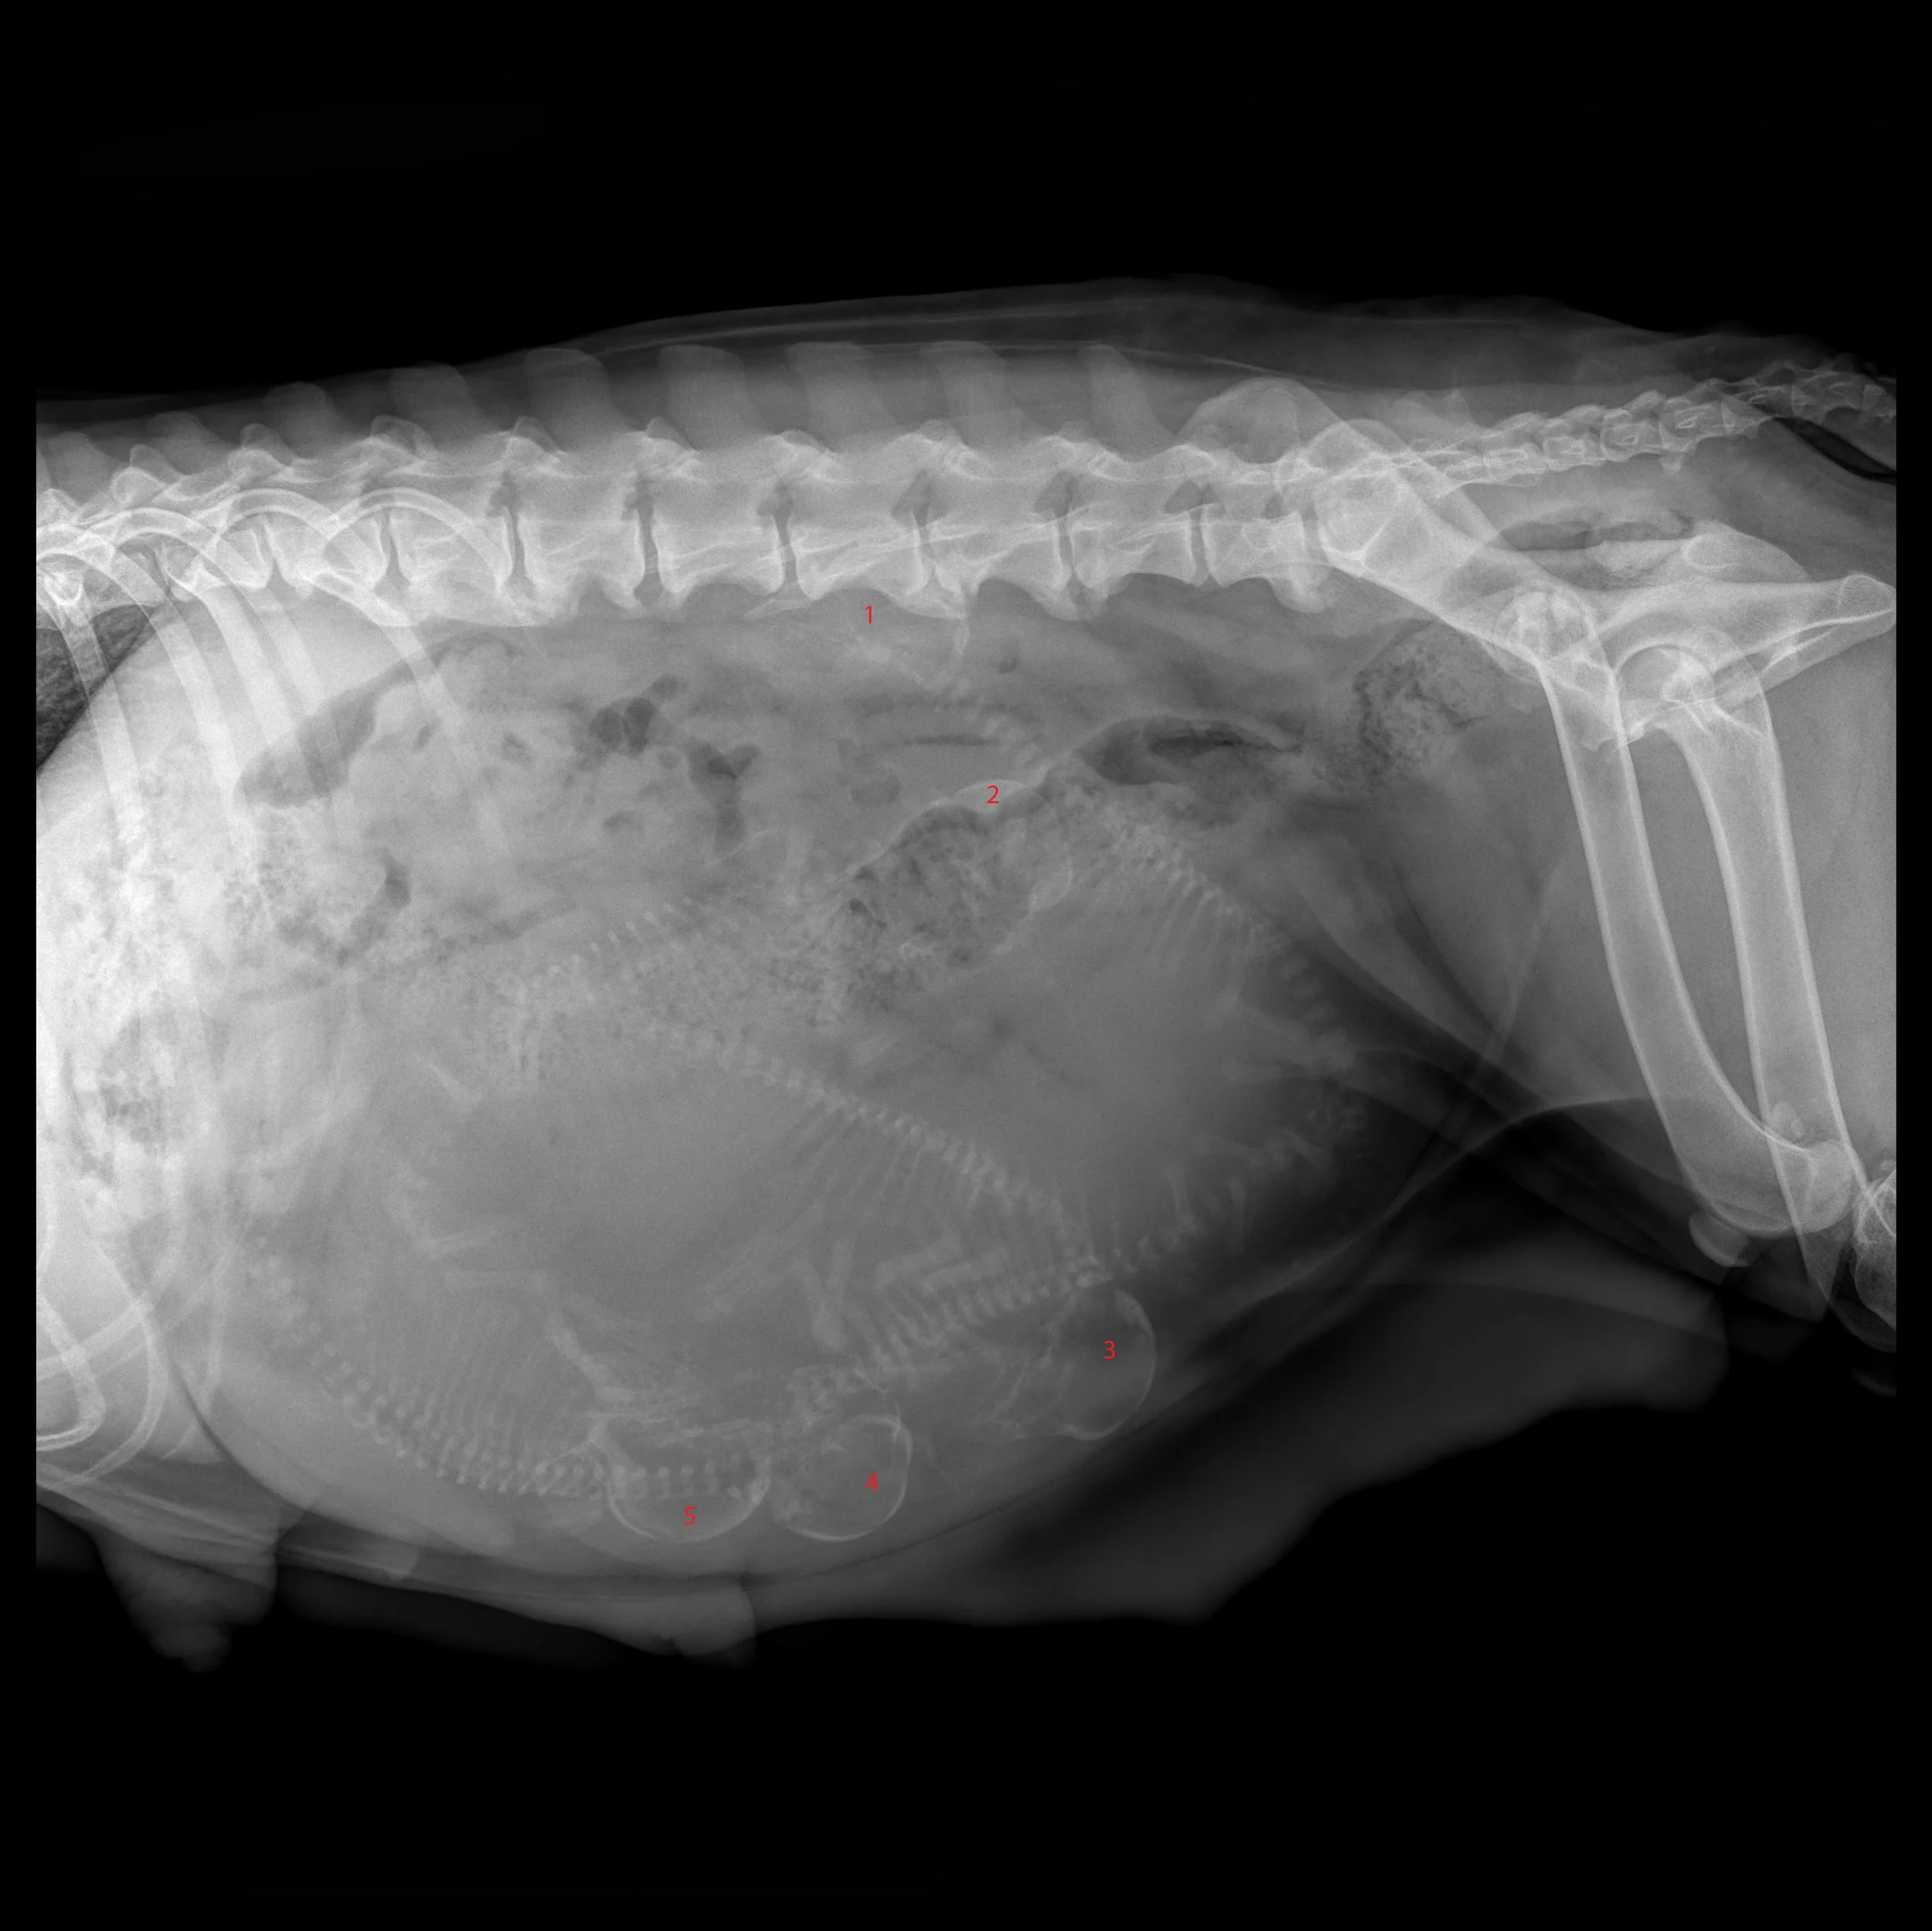

puppy count x ray

As well as eye testing for both breeds to ensure they. Ayasha had her pre-partum puppy count x-ray today and the vet confirmed that we are expecting 4 precious puppies.

It takes about 45 days for the puppies bones to mineralize in the uterus meaning they cannot be seen on x-ray before this point. 50 Days Pregnant Dog Xray. X-rays most often give us an exact count of the litter but even with the best images some puppies could be hiding behind another puppy or the dams spine.

A 50 day pregnant dog xray shows the development of embryos. Up to 6 cash back Puppy count X-rays are the most accurate way to know how many puppies are expected. Have you ever seen an X-Ray of a pregnant dog.

Radiographs can be performed 55 days after ovulation for an accurate puppy. Cammies is our German Shorthaired Pointer and she is having her first litter of puppies. Fetal count radiographic procedures are commonly performed in veterinary medicine.

The best time to perform x-rays for a puppy count is one week prior to the expected due date.